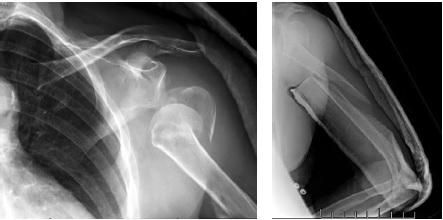

After patient examenation and preparing for surgical treatment open direct repositioning and plate osteosynthesis were performed through the deltoid-pectoral approach with an additional lateral approach. Surgical treatment was performed in the beach-chair position.

The first step was passing the lag screws through the diaphyseal part of the fracture; however, satisfactory repositioning was not achieved. The lag screws were removed and two cerclage sutures were applied (Fig. 2). Then osteosynthesis was performed with a long PHILOS plate (Synthes) (Fig. 3).

Fig. 2. Intraoperative X-rays: a — humerus diaphysis fragments displacement; b — reposition of the humerus shaft, lag screws insertion; c — loss of reposition; d — removal of lag screws, cerclages ostheosynthesis